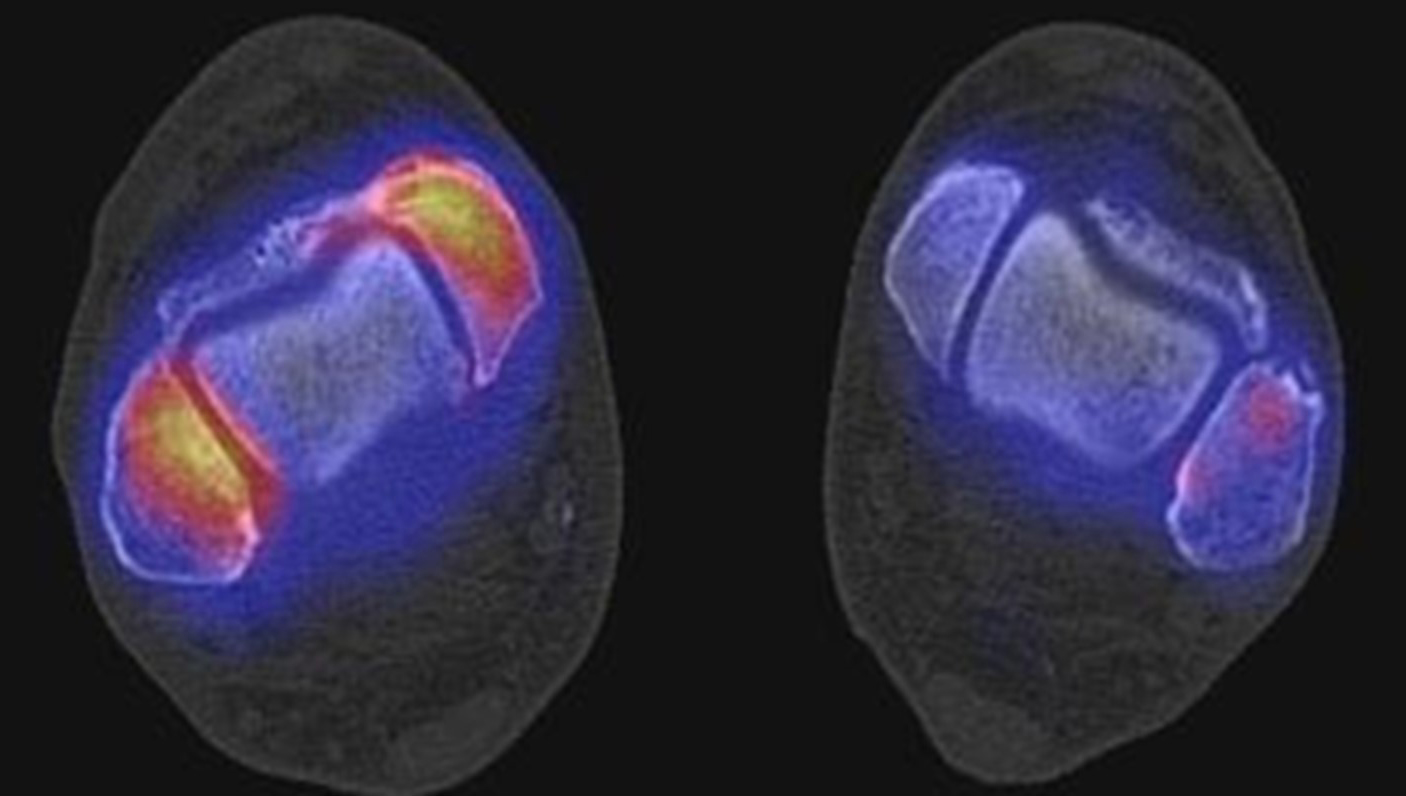

Abbildung 1.8.a und b: Akute Arthritis bei bekannter Gicht in beiden OSG: links die Früh-/Weichteilphase; rechts die Mineralisations­phase. Deutliche, entzündlich bedingte Mehranreicherungen in der Früh-/Weichteilphase. In der Mineralisation­sphase erkennt man die entzündliche Mitreaktion der subchondralen Gelenkabschnitte.

Zum Lesen der Bildbeschreibung und zur Vollansicht bitte das Bild anklicken. Bild: H. C. Rischke

Abbildung 1.8.c - e: Akute Arthritis in beiden OSG, rechts > links. Im SPECT/CT erkennt man die Mitreaktion der subchondralen Gelenkabschnitte. Die Arthritis ist so akut, dass (noch) keine ossären morphologischen Veränderungen im CT abgrenzbar sind.

Zum Lesen der Bildbeschreibung und zur Vollansicht bitte die Bilder anklicken. Bilder: H. C. Rischke